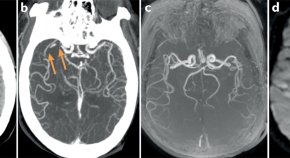

• Artificial intelligence algorithms are well suited to the fast decision making needed in the management of large vessel occlusive stroke. In a new study, a fully automated CT angiography algorithm identified large vessel occlusions with impressive sensitivity, but the work highlights the need for high reporting standards to maximize translatability.